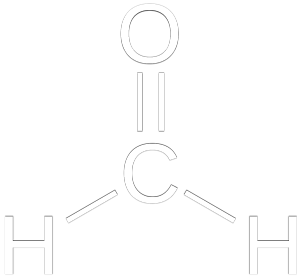

FORMALDEHYDE